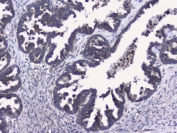

IHC staining of FFPE human ovarian cancer with RALBP1 antibody. HIER: boil tissue sections in pH6, 10mM citrate buffer, for 20 min and allow to cool before testing.